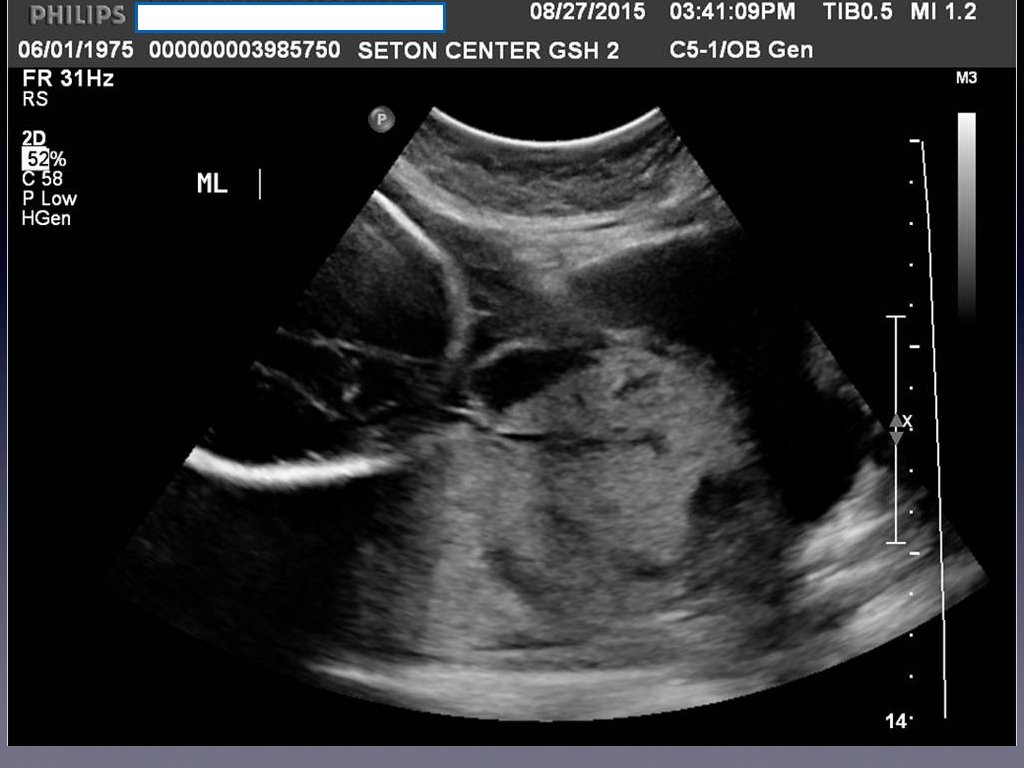

Prenatal Diagnosis • When the diagnosis is made it is usually made by ultrasound in the second or third trimester. • Sonographic findings suggestive are • • loss of normal hypoechoic retroplacental zone • multiple vascular lacunae (irregular vascular spaces) within the placenta “swiss cheese” appearance • blood vessels or placental tissue bridging the uterine-placental margin, myometrialbladder interface, or crossing uterine serosa • retroplacental myometrial thickness < 1 mm • numerous coherent vessels visualized with 3 -D color/power Doppler in a basal view. If sonographic findings are inconclusive or a placenta percreta is suspected, MRI may be useful.

Ultrasound Findings Suggesting Morbidly Adherent Placenta First trimester • • Gestational sac that is located in the lower uterine segment • Multiple irregular vascular spaces noted within the placental bed • Implantation of gestational sac imbedded into cesarean delivery sac (“cesarean scar ectopic”) Second trimester • • Multiple vascular lacunae within placenta

Ultrasound Findings Suggesting Morbidly Adherent Placenta • Third trimester • Loss of normal hypoechoic retroplacental zone • Presence of multiple vascular lacunae within placenta (Swiss-cheese appearance) • Abnormalities of uterine serosa-bladder interface (intertuption of line, thickening of line, irregularity of line, and increased vascularity • Extension of villi into myometrium, series, or bladder • Retro-placental myometrial thickness of< 1 mm • Turbulent blood flow through lacunae on Doppler ultrasonography • Increased subplacental vascularity • Vessels bridging form placenta to uterine margin • Gaps in myometrial blood flow